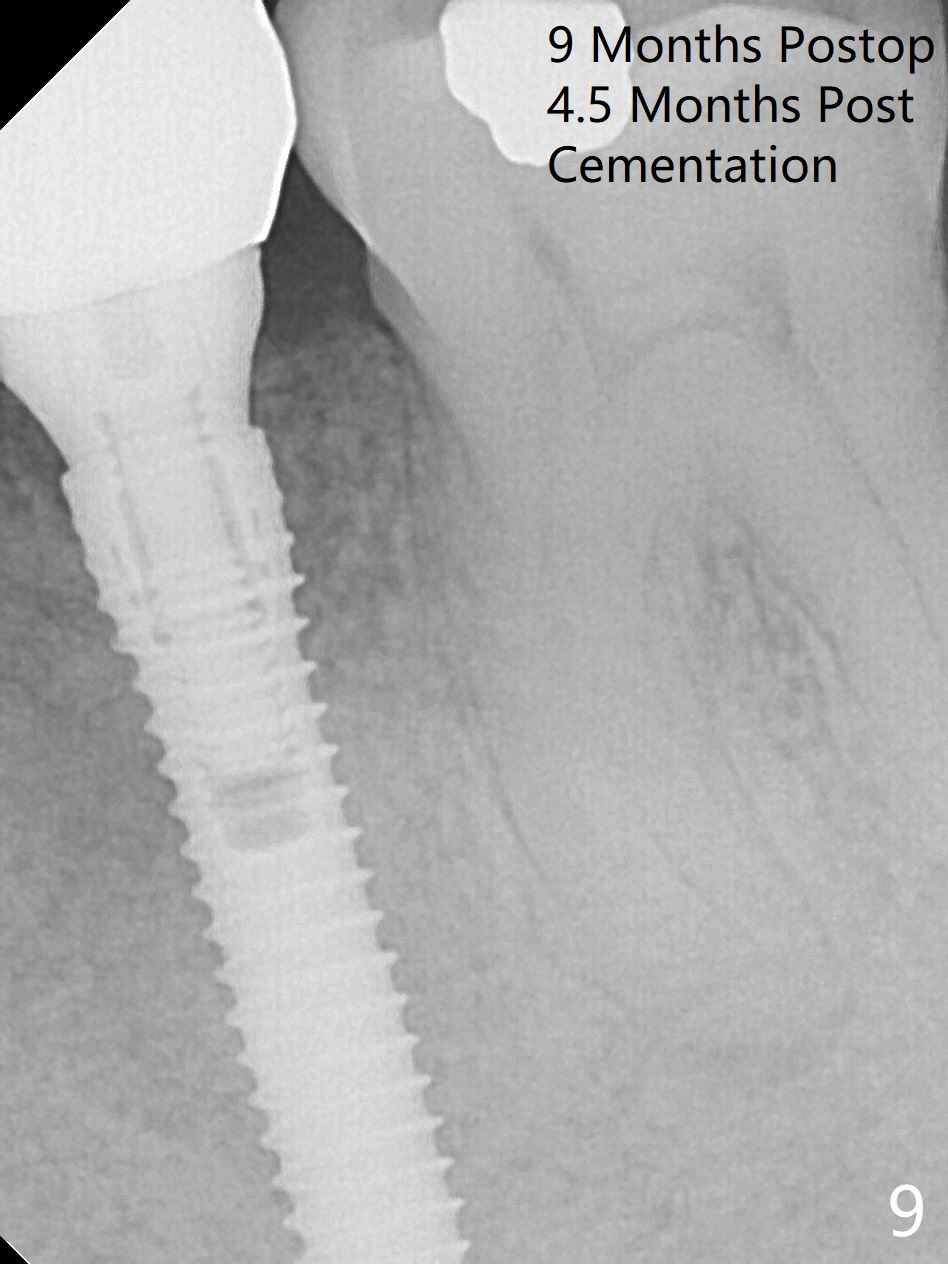

Extraction of the lower left 2nd premolar with vertical fracture (Fig.1,2 >) is easy because of peri-radicular radiolucency. The apical end of the osteotomy is not shown with a 2 mm pilot drill (Fig.3) or a 3.8x18 mm implant (Fig.4) in place. It appears that the implant is not placed deep enough. Following 3-4 more turns of the implant and placement of a 5.5x4(3) mm abutment (Fig.5 A), allograft is placed (*). A postop panoramic X-ray is taken (Fig.6); the osteotomy could have been deepened to reduce the possibility of periimplantitis. Retrospectively, the panoramic X-ray should be taken after use of the pilot drill. The bone around the implant appears to have regenerated 4 months postop (Fig.7,8). Bone density appears to continue increasing 9 months postop (i.e., 4.5 months post cementation, Fig.9). Bone loss is minimal 2 years post cementation (Fig.10).